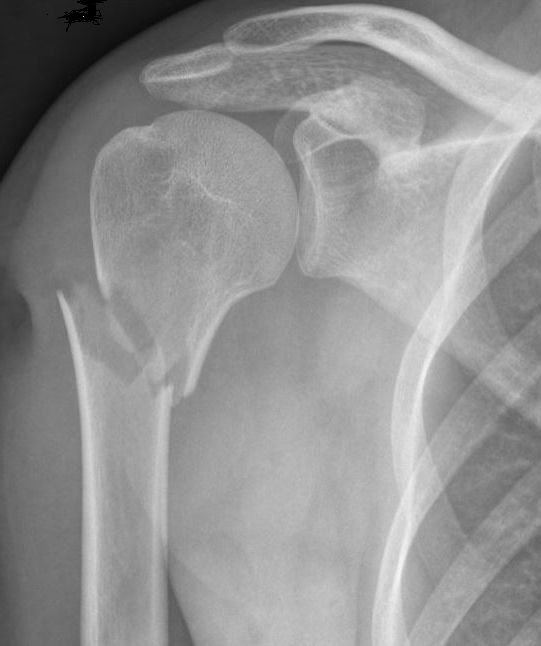

In het geval dat de breuk door de kop zelf heen loopt, is de behandeling afhankelijk van hoe de breukdelen ten opzichte van elkaar liggen en in hoeverre die nog een goede stand hebben. Indien de vorm van de kop nog goed is, kan de traumachirurg besluiten u zonder operatie uit te behandelen. In dat geval krijgt u ook een draagband of een mitella. Indien de breukdelen echter ernstig verplaatst zijn en de vorm van de kop ernstig verstoord is, kan het zijn dat u geopereerd dient te worden. Of u een operatie dient te krijgen, is onder andere afhankelijk van de stand van de breuk, uw activiteitspatroon en uw lichamelijke toestand.

Indien u geopereerd moet worden, zal de traumachirurg de vorm van de kop willen herstellen en de kop of de fragmenten van de kop weer vast willen zetten aan de schacht. Hiervoor heeft uw traumachirurg verschillende opties, afhankelijk van het type breuk en de voorkeur van uw chirurg. Vaak gebruikt worden platen en schroeven om de verschillende breukdelen aan elkaar vast te zetten. Soms kan de chirurg ook besluiten de breuk met een pen en schroeven vast te zetten. Hiervoor is vaak een kleinere snede nodig dan bij een plaat met schroeven.

Wanneer de kop in meerdere stukken is gebroken en uw chirurg inschat dat vastzetten met een plaat en schroeven of pen niet haalbaar is, kan het zijn dat u direct in aanmerking komt voor een kunstkop/schouderprothese. Uit onderzoek blijkt echter dat dit alleen zinvol is bij de zeer ernstige breuken en dat de functionele resultaten hiervan niet altijd even goed zijn. Welke operatie u krijgt, is dus afhankelijk van de eigenschappen van de breuk, uw eigen toestand en de voorkeur van de chirurg.